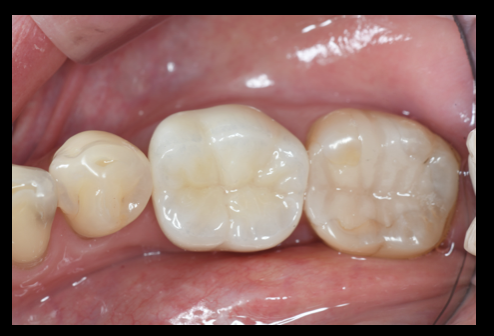

CEREC, セレック,プライムスキャン, プライムミル,オムニカム, セラミック, 即日修復, One Day Treatment, Vital Pulp Therapy:歯髄温存療法,ダイレクトボンディング

歯の根の治療(神経の治療)